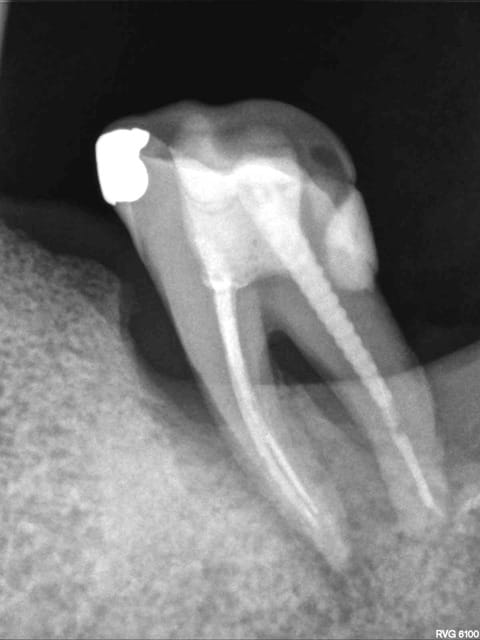

Petite présentation rx pour savoir ce que vous pensez de ce cas. R26 = 14/10/2010

R 52 = 07/02/2011

R 69 = 11/05/2013

R71 est de cette semaine, allez y comprendre quelque chose, dame nature a été très gentille sur ce coup là, de l'os s'est reformé.

Une explication à me proposer?

L'angulation est différente, et pour preuve sur la R71 on voit bien les deux canaux mésiaux de manière distincte, alors qu'ils étaient toujours confondus sur les autres radio...

Il n'y a jamais de "miracle" en paro! Pour une lésion endo oui, mais pas pour une lésion paro...